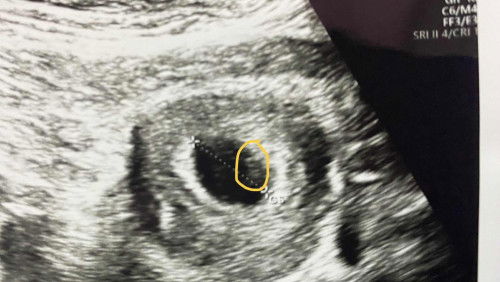

Baca Hasil USG

Bun.. aku mau tanyaa, aku hamil di perkirakan 7 minggu waktu USG, dokternya cuma bilang " Alhamdulillah ya didalem, belom ada detak jantungnya". Ini sebenernya yang kecil itu janinnya ga sih Bun? Aku ga tanya lanjut hasil USG nya langsung masuk amplop, waktu di monitor nya ga keliatan